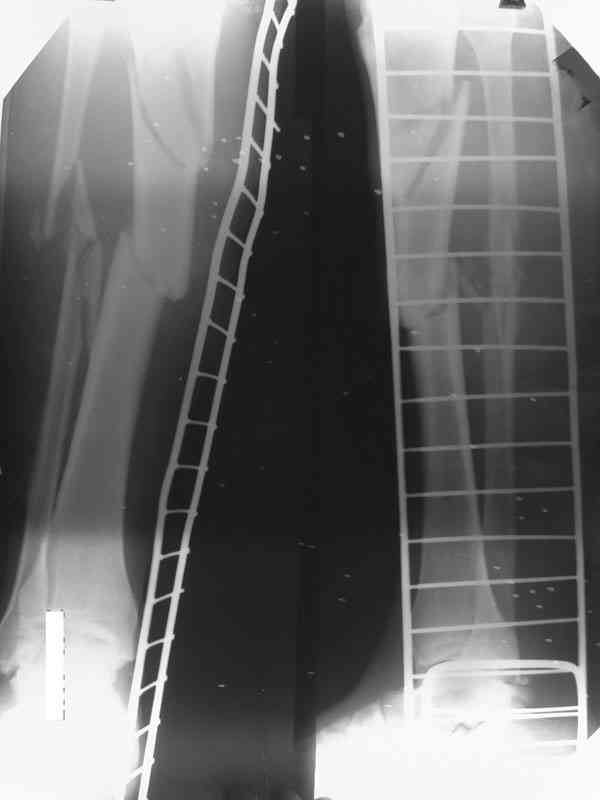

Как дополнение высылаю снимки и фото конечности, чтобы Вы могли оценить состояние м/т, и течение заболевания.